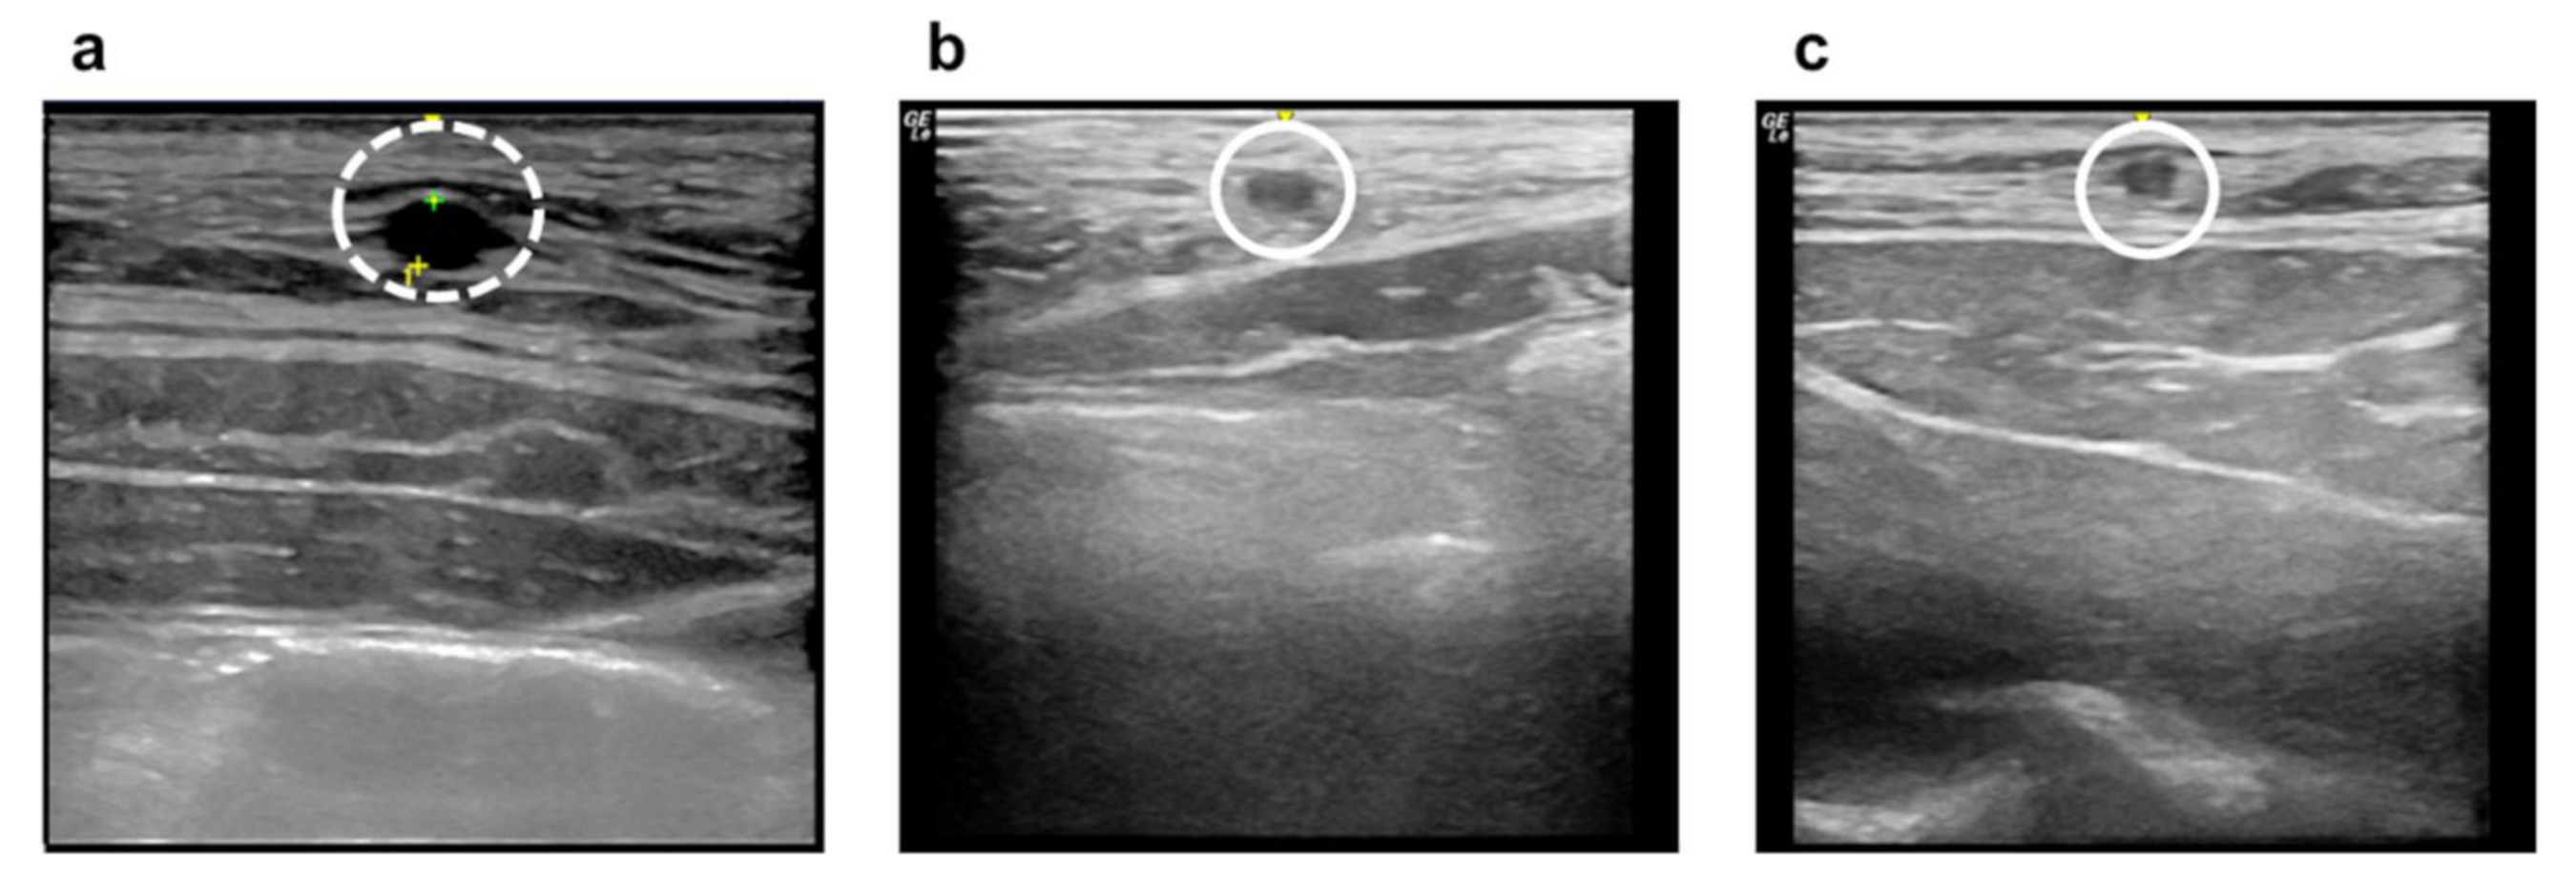

3.3. Examination of Vascular Occlusion